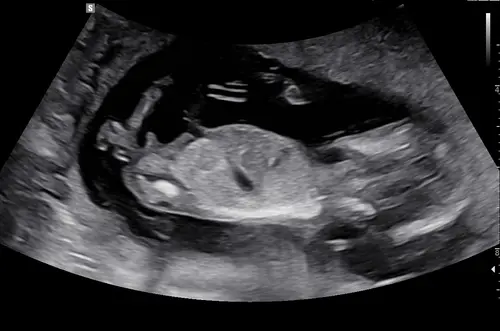

Iemand een idee? In de vorige topic 2x meisje 1x een jongentje werd er gezegd maar vandaag een nieuwe echo gehad bij de 13.4 weken vandaar nogmaals de vraag 😊

Reactie op Wensmoeder0546

Iemand een idee? In de vorige topic 2x meisje 1x een jongentje werd er geze ...

Geen nub te zien

Kan je toevallig hierin wel wat zien haha?

Deze had je keertje al geposted hihi, ik denk wel jongen

Ah oké! Deze foto’s waren met 13+2